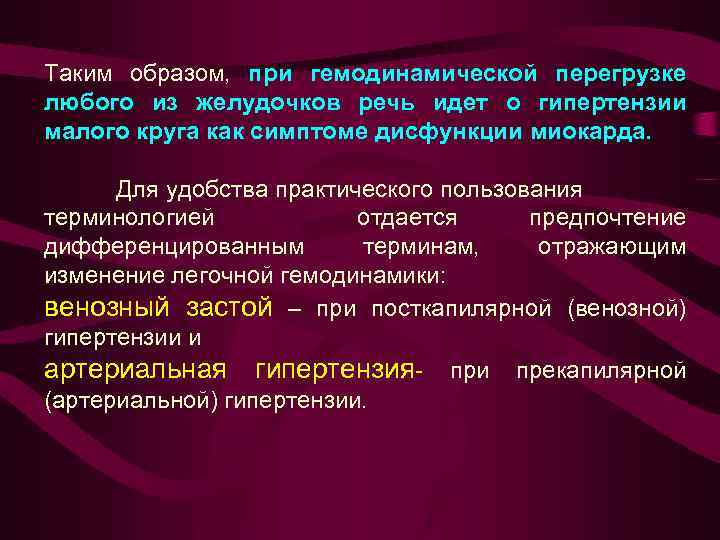

Таким образом, при гемодинамической перегрузке любого из желудочков речь идет о гипертензии малого круга как симптоме дисфункции миокарда. Для удобства практического пользования терминологией отдается предпочтение дифференцированным терминам, отражающим изменение легочной гемодинамики: венозный застой – при посткапилярной (венозной) гипертензии и артериальная гипертензия- при прекапилярной (артериальной) гипертензии.

Таким образом, при гемодинамической перегрузке любого из желудочков речь идет о гипертензии малого круга как симптоме дисфункции миокарда. Для удобства практического пользования терминологией отдается предпочтение дифференцированным терминам, отражающим изменение легочной гемодинамики: венозный застой – при посткапилярной (венозной) гипертензии и артериальная гипертензия- при прекапилярной (артериальной) гипертензии.